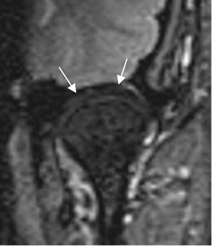

Adicionalmente, realizar secuencias coronales para valorar el componente rotacional, con desplazamiento medial o lateral. (1). (Fig 5).

Fig 5. Disco normal.

RM coronal en T2.